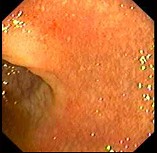

慢性腹泻患者,解黏液脓血便伴里急后重,多次粪便常规与培养均未发现致病菌及原虫。 肠镜检查如图,经柳氮磺胺吡啶治疗症状明显改善,本例诊断最应考虑()。

A:溃疡性结肠炎

B:Crohn病

C:结肠癌

D:肠结核

E:慢性细菌性痢疾